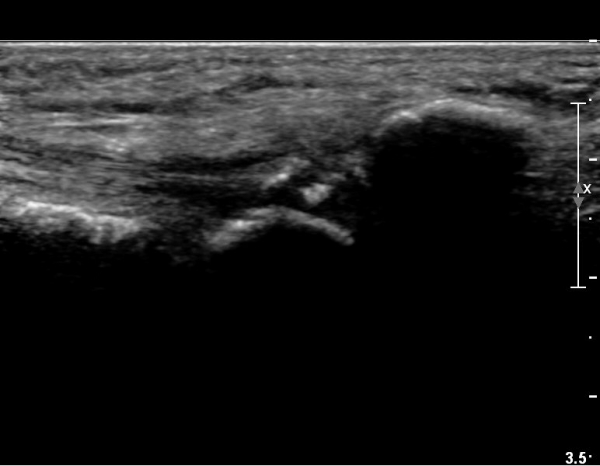

ŽÃËÀÚ¸¦ ¾à°£ ¾ÕÂÊ(¹ß ¿ÜÃø)À¸·Î À̵¿ÇÏ´Ï Á¾ÀÚ»À¿¡ ºÙ´Â Àåºñ°ñ°ÇÀÌ °üÂûµÇ°í °Ç ÁÖÀ§ ºÎÁ¾ÀÌ °üÂûµÊ(»çÁø 2, 3).